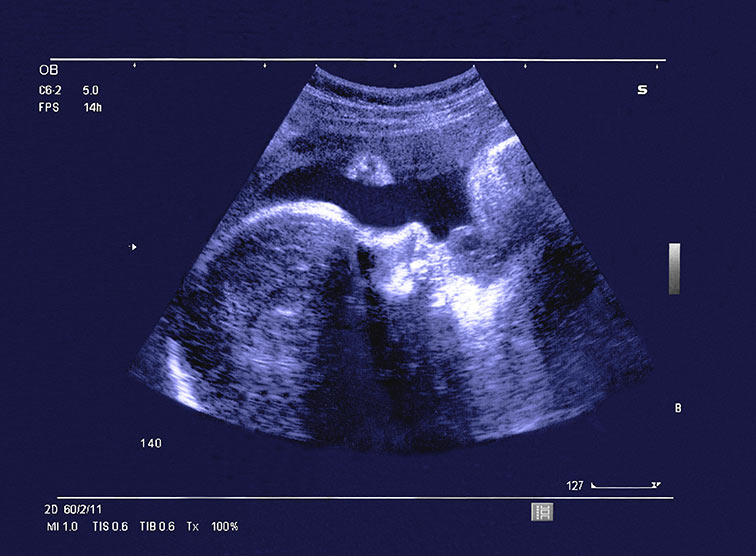

Claudia Versluis nennt in diesem Zusammenhang etwa das Organ Screening, einen Ultraschall, der zwischen der 20. und der 24. Schwangerschaftswoche durchgeführt wird und bei dem alle angelegten Organe des ungeborenen Kindes genauer untersucht werden.